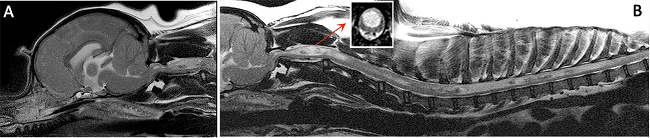

(See above a magnetic resonance imaging [MRI] scan of a

cavalier's brain and spinal cord, with the arrow

pointing to a syrinx [the

elongated white area] within the spinal cord. The blue and gray diagram

at right -- prepared by Dr. Rusbridge -- shows the location of the syrinx

within the spinal cord. In the images of a cavalier

below, the red arrow points from a syrinx to a cross-section of the spine at

that point. This image is Figure 3 from this

November 2018 article.)